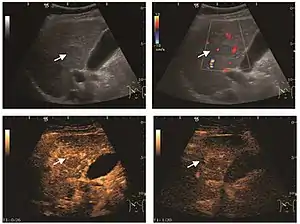

Liver cyst

Hydatid liver cyst. Diagnostic criteria are the presence of membranes and sediment inside.

The ultrasound appearance is a well defined lesion, with very thin, almost unapparent walls, without circulatory signal at Doppler or CEUS investigation. The content is transonic suggesting fluid composition. The presence of membranes, abundant sediment or cysts inside is suggestive for parasitic, hydatid nature. Posterior from the lesion the acoustic enhancement phenomenon is seen, which strengthens the suspicion of fluid mass. They typically displace normal liver vessels but no vascular or biliary invasion occurs.